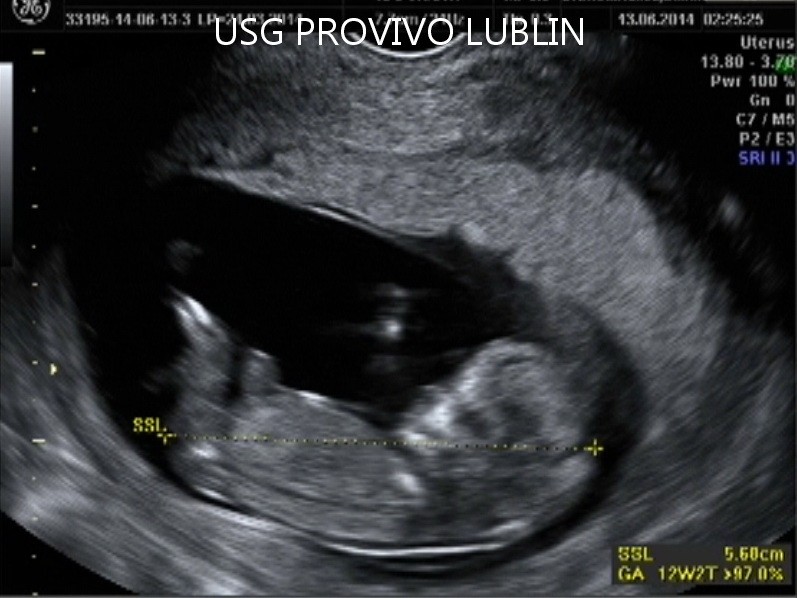

BADANIE USG 3/4D umożliwa dokładny wgląd w rozwój płodu, pozwala na podglądnięcie dziecka w sposób niemalże identyczny z jego aktualnym wyglądem.

W trakcie trwania badania obraz rejestrowany jest na płycie DVD, tak aby każdy przyszły rodzic mógł ponownie odtworzyć badanie w domowym zaciszu. Podczas badania płodu USG 3/4D istnieje również możliwość wydruku zdjęć w formacie kartki pocztowej(148 × 100 mm). Doskonałą jakość, którą charakteryzują się wykonywane przez nas odbitki cyfrowe uzyskujemy dzięki używaniu wyłącznie markowych papierów fotograficznych.